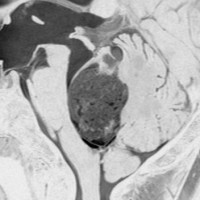

第4脳室腫瘍のMRI像

左は脳幹部腫瘍(退形成性神経節膠腫),右は小脳腫瘍(毛様細胞性星細胞腫)です。どちらも第4脳室を埋め尽くすように発育しています。これらはどちら側から発生したかが明瞭な例ですが,第4脳室腫瘍の中には脳幹部からか小脳からか解らないものもあります。でも多くは小脳側からです。脳幹部側からで注意しなければならないのは上衣腫と血管芽腫です。